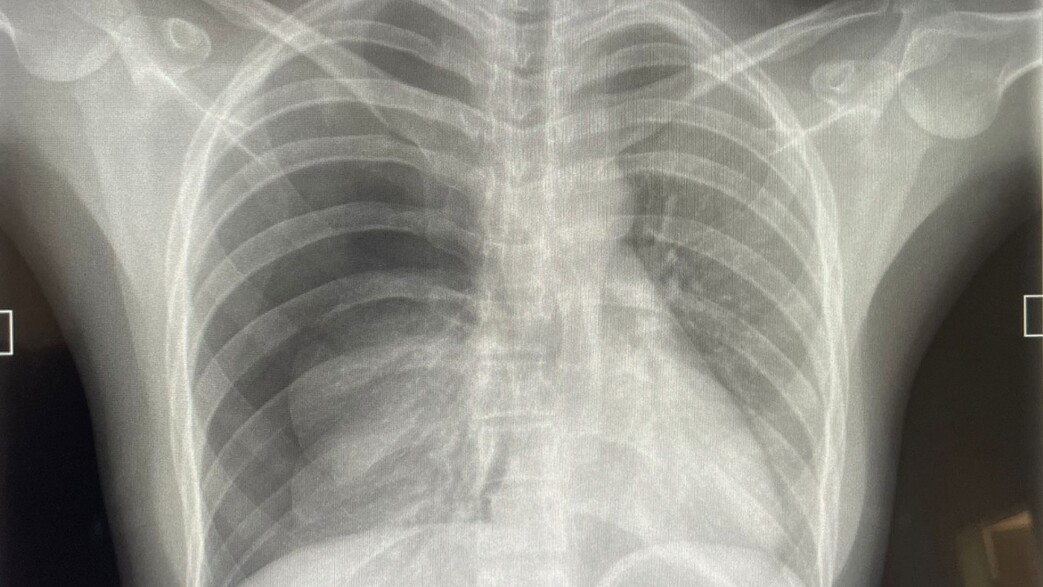

רק לאחר כמה חודשים ותלונות חוזרות של א' על כאבים בחזה עם שיעול לחתי ודמי שנמשך זמן רב, נשלח א' לצילום חזה, ושם התגלה ממצא בריאה השמאלית וניתן לו טיפול אנטיביוטי. למרות שהתגלה הממצא הזה, כך על פי כתב התביעה, לא הונחה א' לבצע צילום חזה נוסף לאחר סיום הטיפול האנטיביוטי ולא זומן לביקורת כדי לבדוק אם הממצא נעלם או מה מצבו הרפואי.

אחרי 7 באוקטובר, זומן א' לשירות מילואים ובמהלך השירות סבל מאותו השיעול ונבדק בידי הרופא הגדודי שהפנה אותו מיד לבדיקה. הממצאים הראו גידול מסיבי בשלב 3 הנחשב למתקדם ובעקבותיו א' נכנס ישר לניתוח.